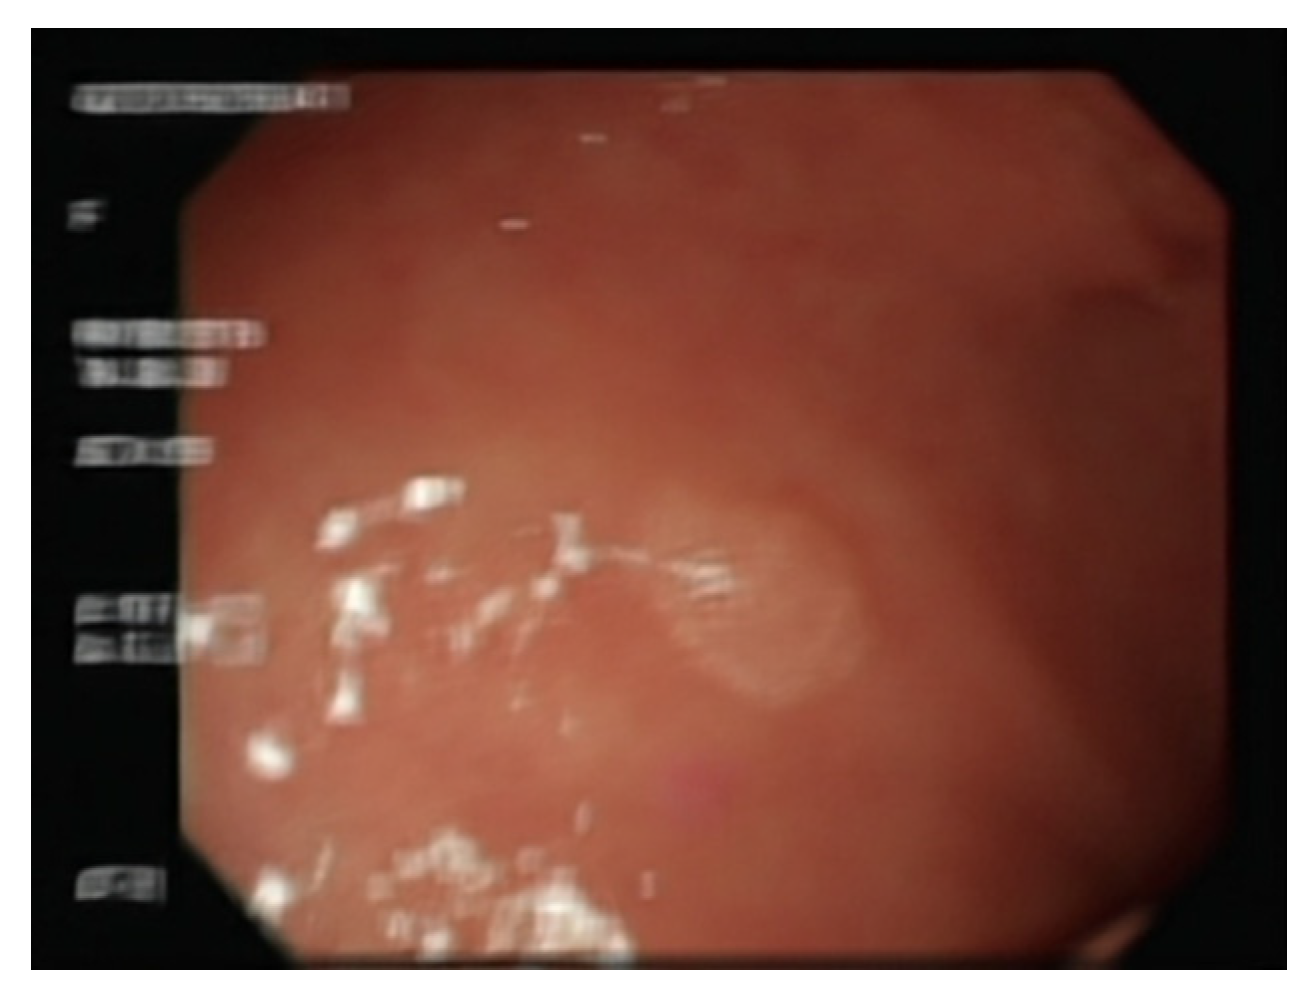

3.13. Evaluating the Deblurring Effect

4.3. Comparison of Gaussian Blur and DeblurGAN-v2